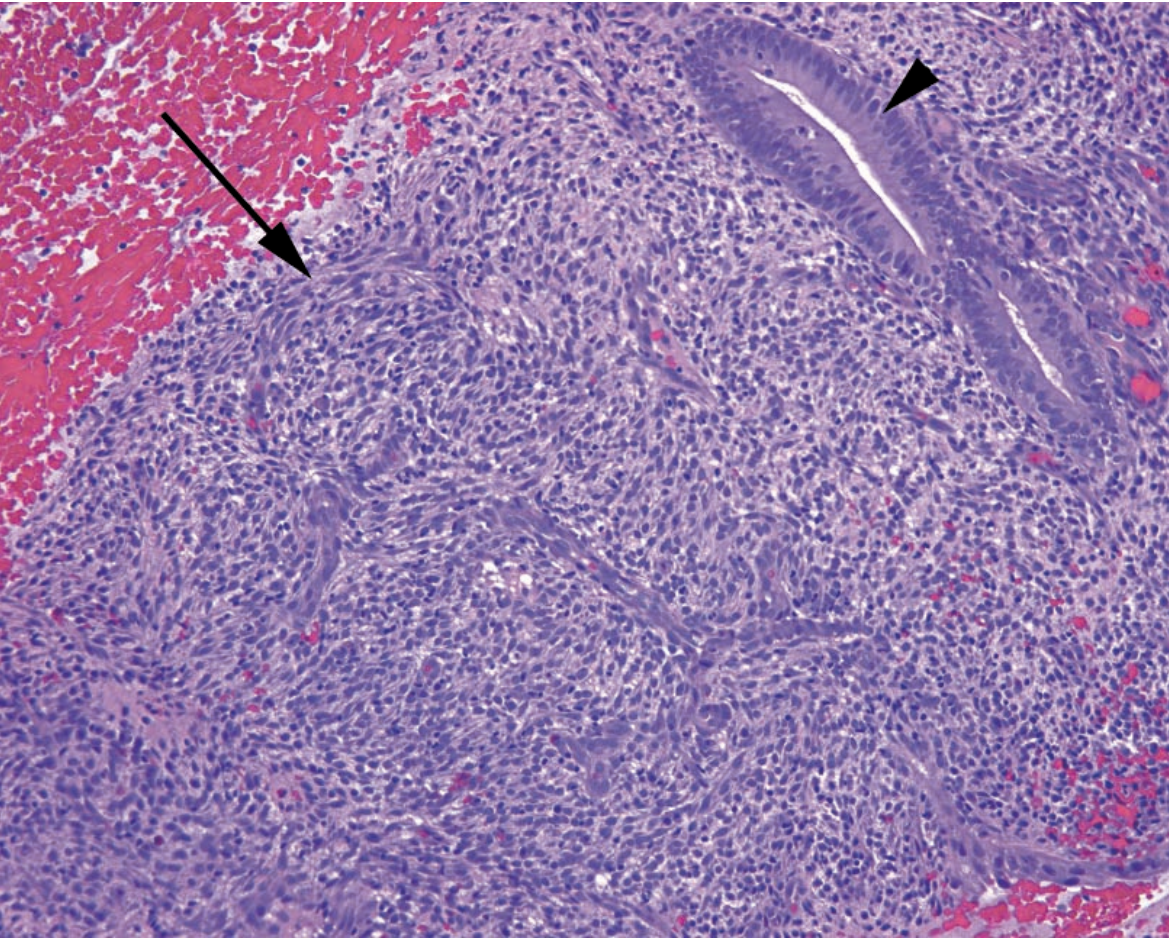

46

MMMT Arrow: Carcinomatous epithelium Circle: Sarcomatous stroma

Describe the morphology of a MMMT.

Mixed tumor consisting of malignant glands in a sarcomatous stroma. Other soft tissue elements (skeletal muscle / cartilage) may also appear.